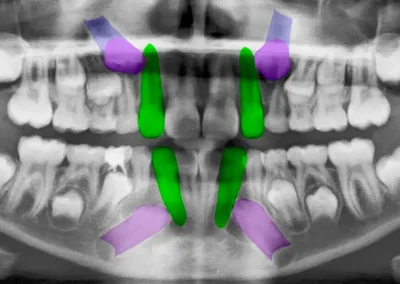

El tratamiento se organiza en etapas claramente definidas. Primero se realiza una evaluación clínica e imagenológica que permite entender la posición dentaria, la relación de mordida y las condiciones biológicas del paciente.

A partir de ese diagnóstico, se define si la ortodoncia está indicada y bajo qué condiciones debe realizarse. Antes de iniciar el tratamiento, se resuelven las patologías que puedan interferir, como caries o enfermedad periodontal.